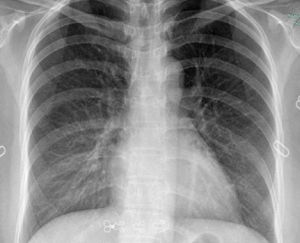

局限性的胸膜增厚和粘連,常見於肋膈角處,使肋膈角變鈍、變淺或變平。透視下可見該處橫膈運動減弱。胸膜亦可有較廣泛的層樣增厚及粘連,若厚度不大,又位於前胸壁或後胸壁,則可以不引起明顯的X線改變,當胸膜增厚達到一定厚度時,則使患側肺野密度增高,當轉至切線位時,可在胸廓內緣和肺野之間有一層邊緣清晰的銳利陰影。大量的胸膜增厚和粘連可引起肋間隙的縮小,縱隔向患側移位,脊柱向對側側凸,橫隔上升。病變廣泛者可使患例肺門上提,氣管向患側移位。另有一種索狀胸膜粘連,在氣胸和肺受壓萎陷時較易見到,顯示為胸壁與一處肺表面之間有一條邊緣清晰的索狀緻密影相連。索狀胸膜粘連往往是貼近胸膜的肺部病灶所引起的胸膜改變。常見於結核並好發於上肺。透視下觀察橫膈運動可以鑑別局限性胸膜增厚和粘連與少量胸腔積液.治療